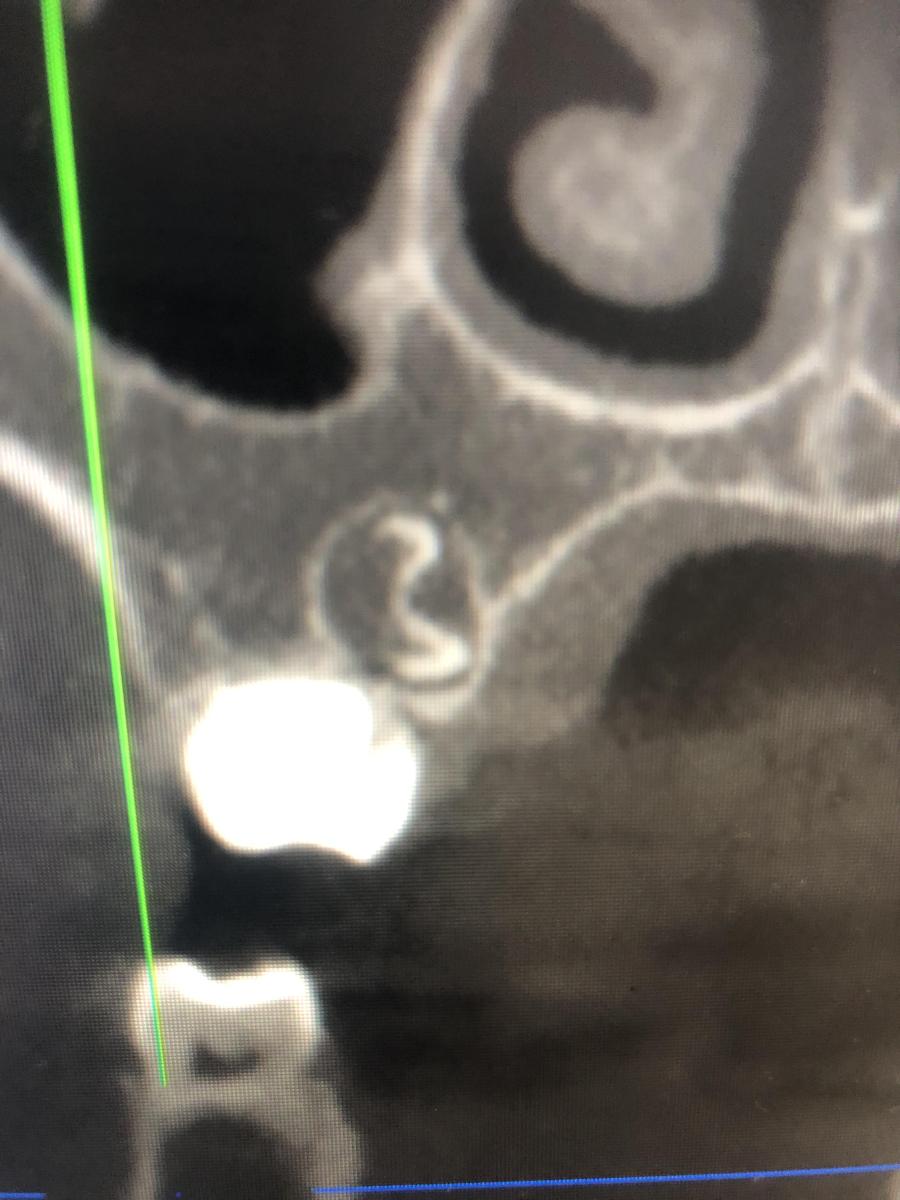

Здравствуйте, Ребекку 7 лет. Отсутствуют нижние зачатки 5 зубов. Верхний зачаток пятерки в недоразвитом состоянии и перевернут . Что с ним будет? Возможно ли что вырастет как надо? И основной вопрос- верхний клык (снимок прилагаю) между молочным и коренным обнаружено какое-то образование- это лишний зуб? Как его удалять? Вырывать молочный клык сейчас , далее удалять лишний и уже после ждать прорезывания постоянного? Или ждать пока молочный сам выпадет?

SGanem, мы были у двух ортодонтов. Один говорит ждать до 8 лет, другой - что ждать не надо надо идти под наркоз сейчас и удалять молочный и лишний клыки

Kseniya2, удалять обязательно и чем скорее, тем лучше!